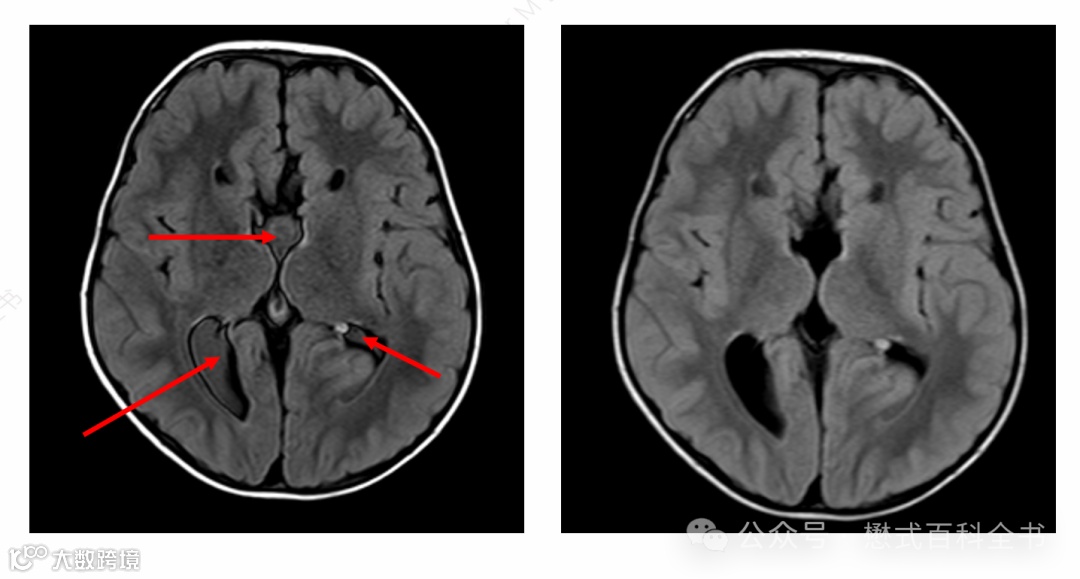

图9:T1-FLAIR(T1-IR)序列可见反弹点伪影[2]

这种伪影的表现,有时候很像是TI设置不合理导致的液体信号抑制不彻底。如同T2-FLAIR序列一样。

图10:T2-FLAIR中TI设置不合理导致脑脊液勾边